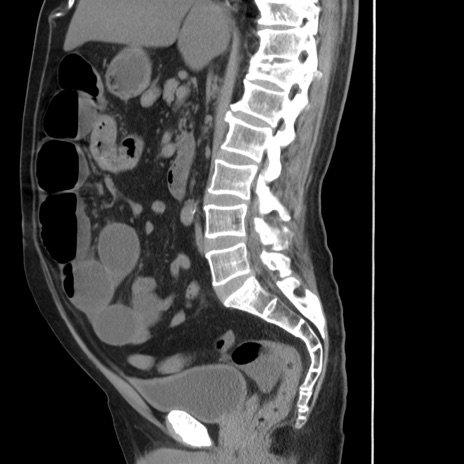

症例20(矢状断像)

【症例】 60歳代男性

【主訴】 腹部膨満、嘔吐

【現病歴】5日前頃より倦怠感を認め食事量減少し4日前の朝嘔吐、食事摂取困難となった。 3日前近医受診し点滴施行され整腸剤などを処方された。 当日他院を受診し、腹部膨満著明、炎症反応の上昇(CRP10.8、WBC11200)あり、紹介受診となる。

【身体所見】 意識JCS1 受け答えがはっきりしないBP 111/57mHg、 P 67bpm、、BT35.2°C、SpO2 97%(RA)、 腹部:膨隆、打診で鼓音あり、全体的に圧痛有り、腸蠕動音(-)、反跳痛ははっきりせず。

【データ】WBC 11400、CRP 14.20